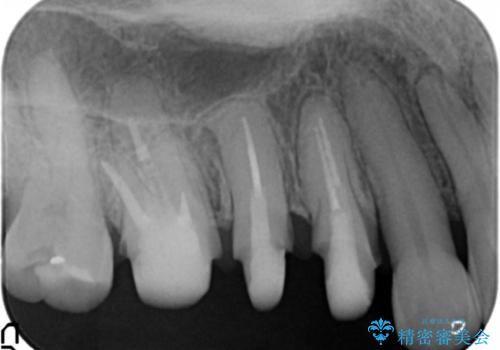

古くなったセラミッククラウンのやりかえ

- 老朽化し黒ずんできたクラウンのやりかえを希望され来院されました。

将来的に歯ぐきの位置が変化しても審美障害となりづらいオールセラミックジルコニアクラウンによるやり替えを計画します。